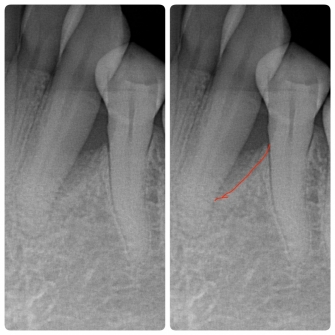

◎歯周組織の再生を促す薬剤「リグロス(保険適応)」を使って歯周組織が再生された一例

☆左写真 歯周組織再生療法前 歯槽骨が吸収しています(赤い線)

☆右写真 歯周組織再生療法後 2年半後 歯周ポケット改善 歯周組織改善傾向

歯周病によって破壊された歯槽骨(歯を支える骨)は、自然に元の状態に戻ることはありません。しかし、再生療法を行うことで、骨を元のように戻せる可能性があります。当院では「リグロス(保険適応)」という薬剤を使用した再生療法を行うことができます。リグロスには、歯周組織の再生に必要な細胞の増殖を促進する「b F G F」というタンパク質が含まれています。この成分が、歯周病によって破壊された歯槽骨や歯根膜(歯と歯槽骨を結ぶ組織)を再生させます。